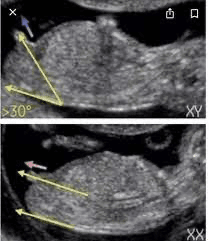

Znalazłam teraz takie zdjęcie i chyba trochę lepiej obrazuje, co i jak, niż w tym artykule z Mama Ginekolog. Co myślicie?

No właśnie też teraz zaczynam się zastanawiać, czy w ogóle dobrze to sprawdzam, bo jak wg kręgosłupa to rzeczywiście nie odstaje. Jak coś to sorki za wprowadzanie w błąd, to dla mnie nowy temat :)

Na Google jakiś czas temu podejrzałam jak wnioskuję się płeć po usg 😅 i widziałam że względem kręgosłupa się patrzy...ale ja tam też się nie znam dla mnie to też nowy temat chodź mam już 2 chłopaków 🙈😅

No i właśnie o tym mówiłam że względem kręgosłupa 😊 widziałam właśnie te zdjęcie i na tym się wzorowałam co do swojego też USG dziejszego ale kompletnie nie mam pojęcia co u mojej dzidzi widać bo lekarz mówił że zasłania się pępowiną 🙈😅 co wróżysz Kochana mi tutaj? 😄